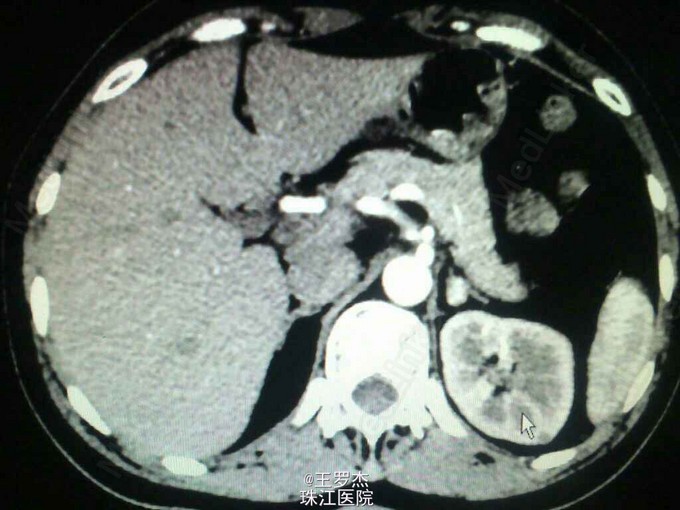

主诉:发现左肾及肾上腺占位3年 患者3年前因VHL综合征行常规体检时CT提示左肾低密度结节影,边界模糊,大小1.2x1.5cm,左肾上腺类圆形结节影,大小0.8x1.0cm,增强扫描明显强化。 既往史:12年前"因视力下降9年,间断性头痛2月"在我院住院,行视右侧小脑半球及左额血管母细胞瘤切除术,左侧视网膜母细胞瘤激光治疗。 家族史:家族多人确诊为VHL综合征。

查体:体温36.8℃,呼吸19次/分,脉率79次/分,血压132/82mmHg。左眼白瞳,视力仅光感,胸腹部查体未见异常。 实验室检查:皮质醇(8:00)519nmol/L,皮质醇(16:00)183nmol/L,24小时游离皮质醇1131nmol/L。 辅助检查:CT提示左肾结节影较前增大,2.9x2.3cm,明显强化。

术前诊断:左肾癌,嗜铬细胞瘤。 由于不典型嗜铬细胞瘤可表现血压正常,为减少手术风险,术前给予利脉和陪他洛克,监测血压心率。3周后血压控制平稳,完善检查后进行手术。 腹腔镜下肾上腺切除术+肾部分切除术+左肾囊肿去顶减压术。术后诊断:左肾透明细胞癌,左肾上腺结节状增生。